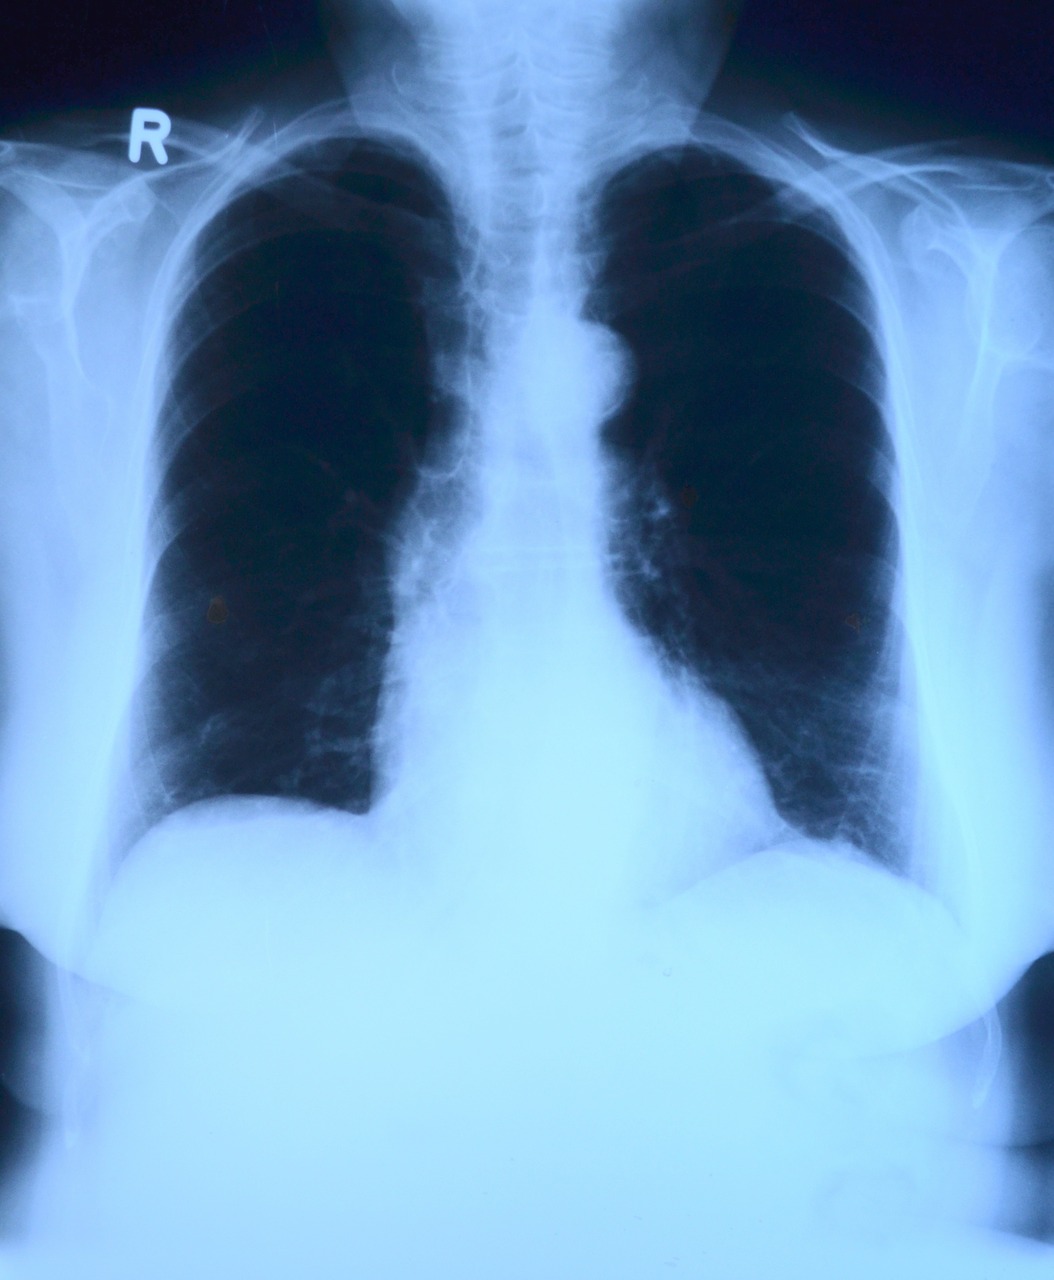

Поэтому очень важно проходить флюорографию. С помощью этого метода можно выявить периферический рак легкого на ранней стадии и вовремя принять меры.

3. Проходите ежегодно флюорографию. Это простое исследование позволяет выявить периферический рак легкого на ранней стадии. Также с помощью флюорографии выявляется туберкулез. Доза облучения, которую вы получаете при флюорографическом исследовании крайне мала, так что от лучевой болезни не умрете =)